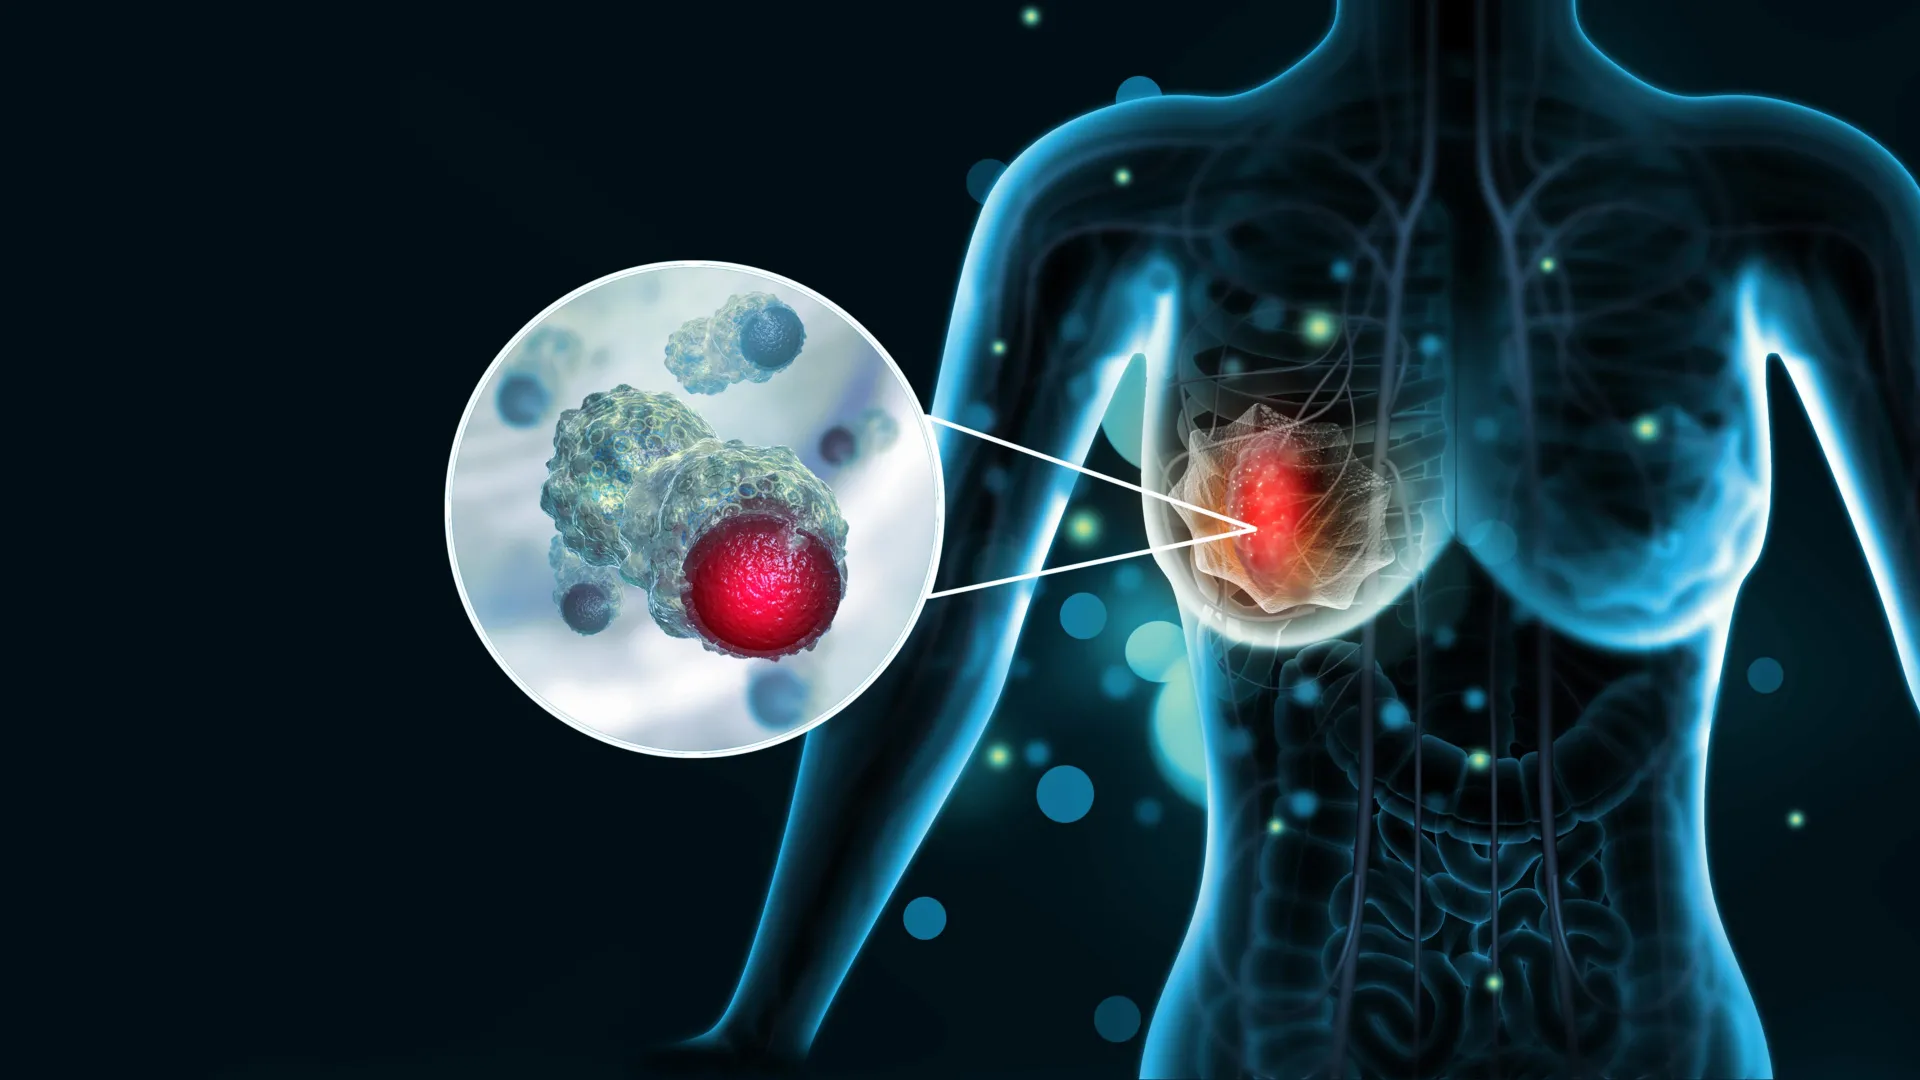

Breast cancer is the most commonly diagnosed cancer in women worldwide. According to the World Health Organization, about 2.3 million women were diagnosed with the disease in 2022, and roughly 670,000 died from it. While treatments have improved…